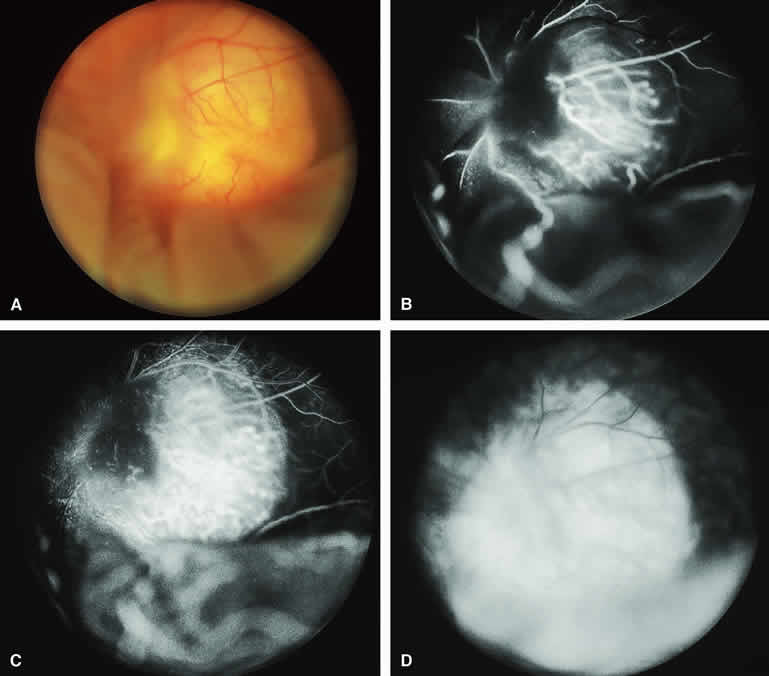

Fig. 2. Typical melanotic choroidal nevus. A. Small gray choroidal nevus one disc diameter above fovea. The pale lesion at upper left margin of photograph is a choroidal melanoma that was the main focus of the following angiogram. B-D. Indocyanine green (ICG) angiogram of lesion. B. Early-phase frame showing intense hypofluorescence of nevus. C. Intermediate-phase frame showing sustained hypofluorescence of nevus. D. Late-phase frame showing sustained hypofluorescence of nevus.

ICG angiography of a typical melanotic choroidal nevus (see Fig. 2) shows better definition of the basal area of the lesion than does fluorescein angiography. The entire lesion appears completely and uniformly dark throughout the ICG angiogram. Only the larger retinal blood vessels overlying the nevus are usually demonstrated on ICG angiography.